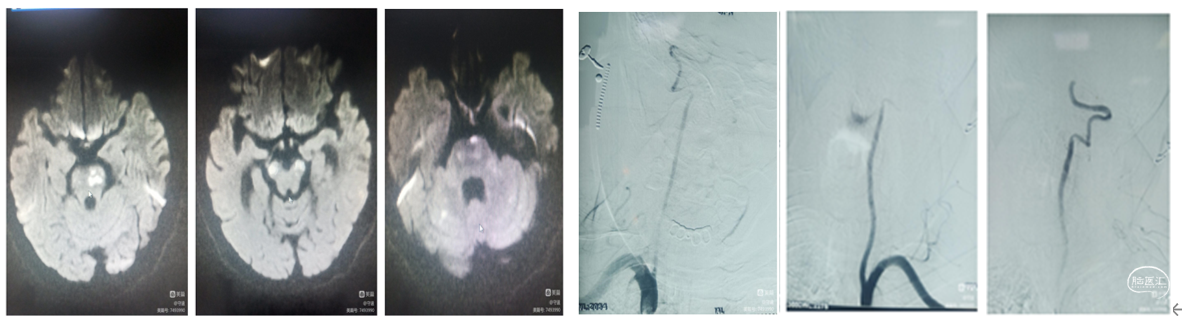

患者入科后评估NlHss评12分,DwI-AsPECT评分6分。考虑为基底动脉闭塞可能。

由于住院后进行性加重,已超过了溶栓治疗黄金时间,行血管内治疗机械再通。核磁检查示:脑干梗塞,DWI-ASPESCTS评分6分。

康复期间进行性加重,已超过了静脉溶栓治疗黄金时间,拟行血管内治疗机械再通。脑血管造影显示:基底动脉起始部闭塞,下图

血管内支架机械取栓:

将6X30mm支架释放于基底动脉尖部与左侧大脑后动脉起始部。支架放置5分钟使支架充分展开,微造影可见基底动脉血流通畅。微造影可见基底动脉尖和双侧大脑后显影。

抽-拉结合取栓

1.裸支架导丝:缓慢拔出微导管于体外,最大限度增加中间导管管腔,有利于抽吸。

2、充分抽吸:跟进中间导管至基底动脉超始部,利用50mL自制负压卡口注射器连接中间导管进行负压抽吸。抽吸出黯红色血栓。

3.回拉支架:负压抽吸中间导管的同时,将取栓支架缓慢拉入中间导管撤出体外。

4.抽吸清理通路:接续二次抽吸中间导管直至血流通畅。

检查取栓结果:

抽吸除少了血栓,造影显示:基底动脉血流通畅。远端供血良好,双侧大脑后动脉供血良好。基底动脉中下段重度狭窄。

术后患者意识模糊,高热39℃,高血糖达30mmol/L。最终预后不良。